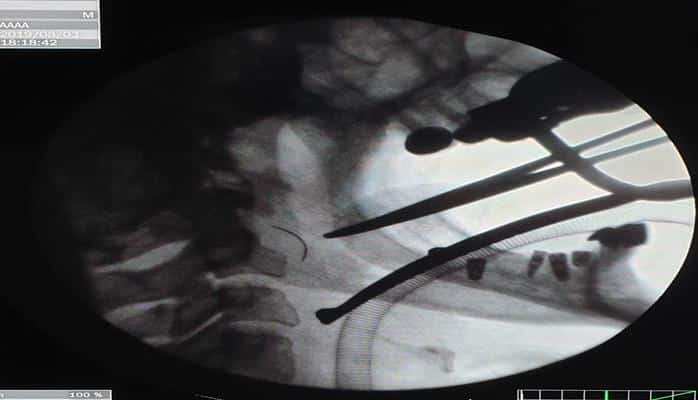

Как сообщает Report, хирург удалил фрагмент иглы длиной около 2 см, оставшийся в горле пациентки во время операции по удалению небной миндалины (тонзиллэктомия), проведенной десять лет назад.

По словам Э.Акбарова, тонзиллэктомия сама по себе непростая операция: "Но в большинстве случаях операцию проводят под местным наркозом и в несоответствующих амбулаторных условиях. Эта операция требует специальных навыков. Во время тонзиллэктомии в 2009 году у пациентки началось кровотечение из правого миндаликового ложа. Для остановки кровотечения было принято решение наложить швы на рану. Во время этой процедуры игла сломалась и сломанный фрагмент остался в мягких тканях шеи. Операция длится четыре часа, кровотечение останавливается, но сломанную иглу обнаружить не удается. В послеоперационный период у пациентки отмечались боли в правом отделе шеи, особенно при глотании и наклоне шеи. Но в то время в ходе радиологического обследования медицинскому персоналу не удалось выявить проблему, а пациентке сказали, что проблема является субъективной".

Хирург-оториноларинголог отметил, что инородное тело было обнаружено случайно: "Во время стоматологического осмотра с проведением компьютерной томографии в горле пациентки был обнаружен фрагмент хирургической иглы. Таким образом, предположения, что жалобы пациентки возникали из-за оставшегося фрагмента хирургической иглы, подтвердились. Несмотря на многочисленные обращения, многие специалисты заявляли о рискованности операции и отказывались ее выполнять. Повторная компьютерная томография, проведенная обратившейся к нам пациентке, подтвердила, что инородное тело находилось в опасной зоне. Путем трансоральной фаринготомии с доступом через горло инородное тело было извлечено. Во время операции и послеоперационный период каких-либо осложнений не было. Пациентка находилась под наблюдением врачей до полного выздоровления".